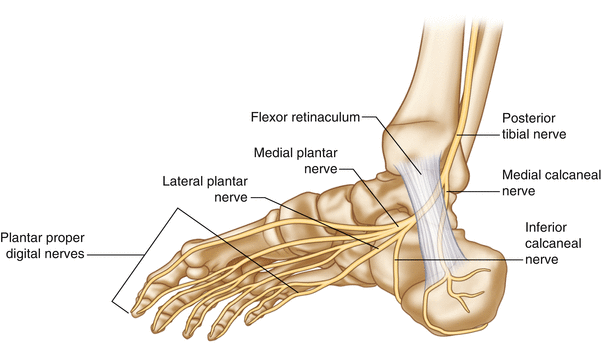

Анатомическое расположение:

Большеберцовый нерв проходит в тарзальном канале под удерживателем сгибателей на медиальной стороне голеностопного сустава [12,13].

Поражение большеберцового нерва и его ветвей

Пальпация медиального подошвенного нерва (MPN)

Медиальный подошвенный нерв является ветвью большеберцового нерва и проходит по медиальной части подошвы стопы. Наиболее частой зоной его компрессии является область бугристости ладьевидной кости, где нерв проходит в узком фиброзно-мышечном туннеле между ладьевидной костью и мышцей, отводящей большой палец стопы [18]. В этой зоне нерв уязвим к механическому сдавлению, особенно при повышенной пронации стопы или гипертрофии мягких тканей.